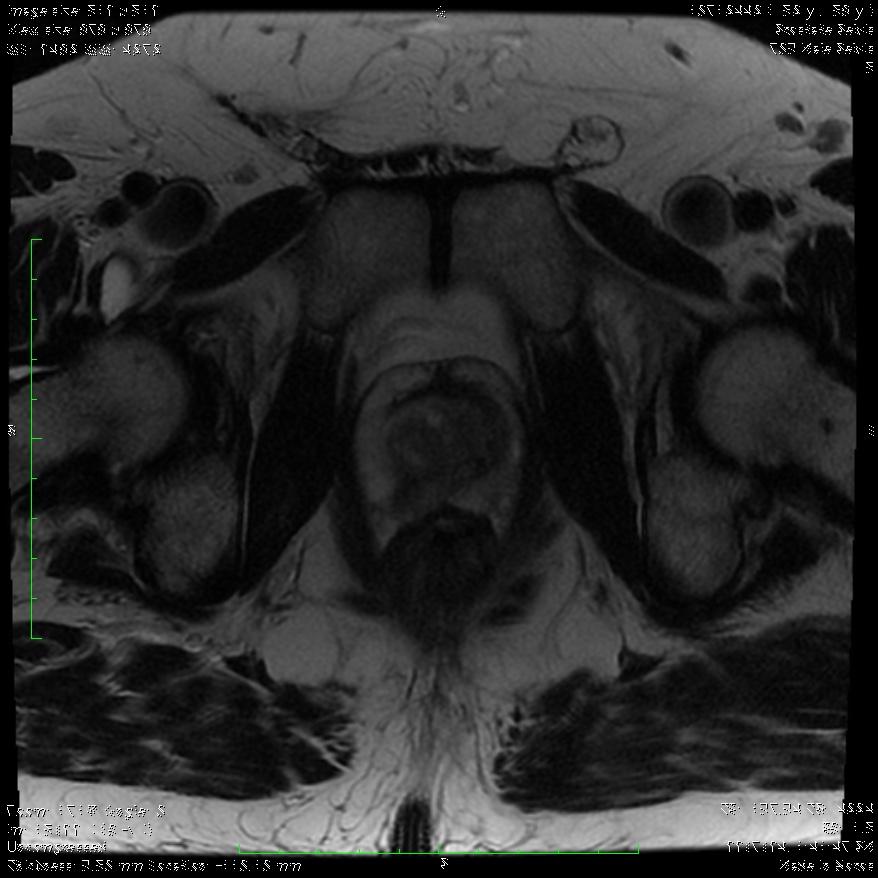

Στη περίπτωση που ο γιατρός εντοπίσει κάποια ένδειξη που θεωρεί ότι χρειάζεται περαιτέρω διερεύνηση, θα καθοδηγήσει τον ασθενή να υποβληθεί σε πολυπαραμετρική μαγνητική τομογραφία (MRI) του προστάτη, προκειμένου να έχει καλύτερη εικόνα της περιοχής.

Χρησιμοποιώντας μια ειδική κλίμακα ταξινόμησης (Prostate Imaging-Reporting and Data System – PI‑RADS) με βάση τα ευρήματα της MRI, ο Ουρολόγος θα αποφασίσει εάν ο ασθενής χρειάζεται να υποβληθεί σε βιοψία.